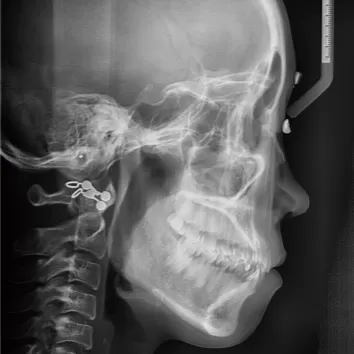

Rayons X avant le traitement

[Radiographie panoramique/Céphalogramme latéral]